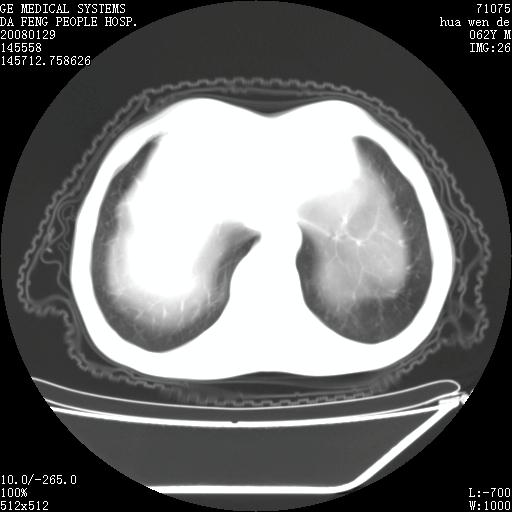

男性,67岁。作肺部检查时发现

右肺脓肿 胸腔胃

考虑:胸腔胃并支气管瘘(并发肺炎,肺脓肿形成)。

理由:1、右上肺内病灶,空洞形成,有液平。

2、肺内多处炎症。

3、前段肺内炎症,支气管引流通畅,与肿块无关系。

1.整个食管扩张,未见明显占位性病变,贲门区亦未见明显占位病变,考虑:贲门失驰缓症;

2.右上肺病变边缘可见毛刺,囊壁厚度不均匀,周围境界较清楚,未见炎性渗出性影,右上肺外带可见片状影,边缘不清,考虑:肺癌伴空洞形成、右上肺炎。

食管全程扩张,壁均匀不厚,喷门失弛缓症

右上肺空洞可见液平,临近肺野磨玻璃密度,考虑1.结核2.脓肿

贲门失驰缓症.肺部感染伴脓肿形成。支持!是否吸入性要结合临床诊断,我们影像是看不出来的。但胸腔胃能排除(1.没有手术史支持,2.双侧胸廓对称,胸壁、肋骨及胸膜规整,3,食管壁明显扩张内壁光滑,胸腔胃黏膜皱襞多较厚)。